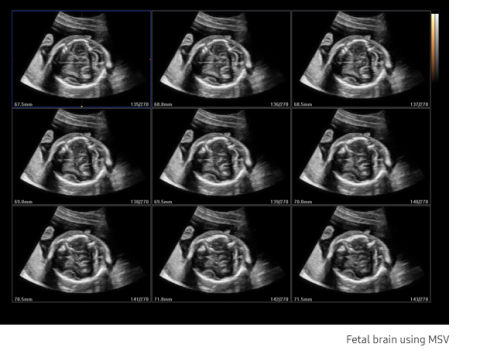

Comprised of a suite of outstanding imaging applications (Multi-Slice View, Oblique View, and XI VOCAL), 3D XI offers precise control over 3D/4D volume data manipulation to improve diagnostic accuracy.